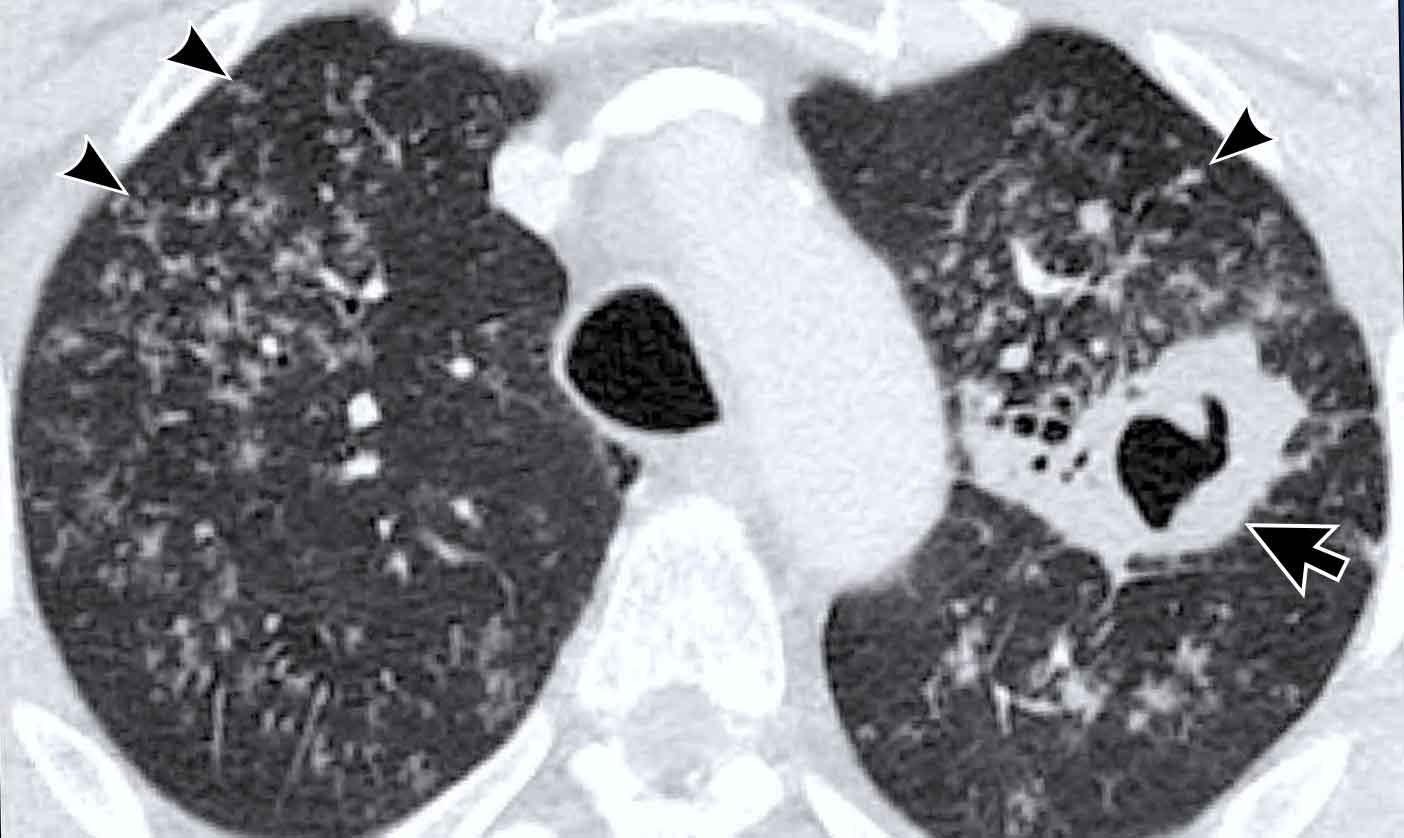

Hình ảnh này của một nam bệnh nhân 60 tuổi có khối trên X-quang ngực.

Sinh thiết dưới hướng dẫn CT được thực hiện do nghi ngờ ung thư phổi.

Hình ảnh

Có một khối tạo hang ở thùy dưới phải.

Lưu ý cũng có các đậm độ dạng “cây nảy chồi” xung quanh khối.

Lao được xác nhận bằng sinh thiết.

Dấu hiệu “cây nảy chồi” (Tree-in-bud)

Hình ảnh “cây nảy chồi” điển hình cho sự lan tràn nội phế quản hoạt động của nhiễm trùng.